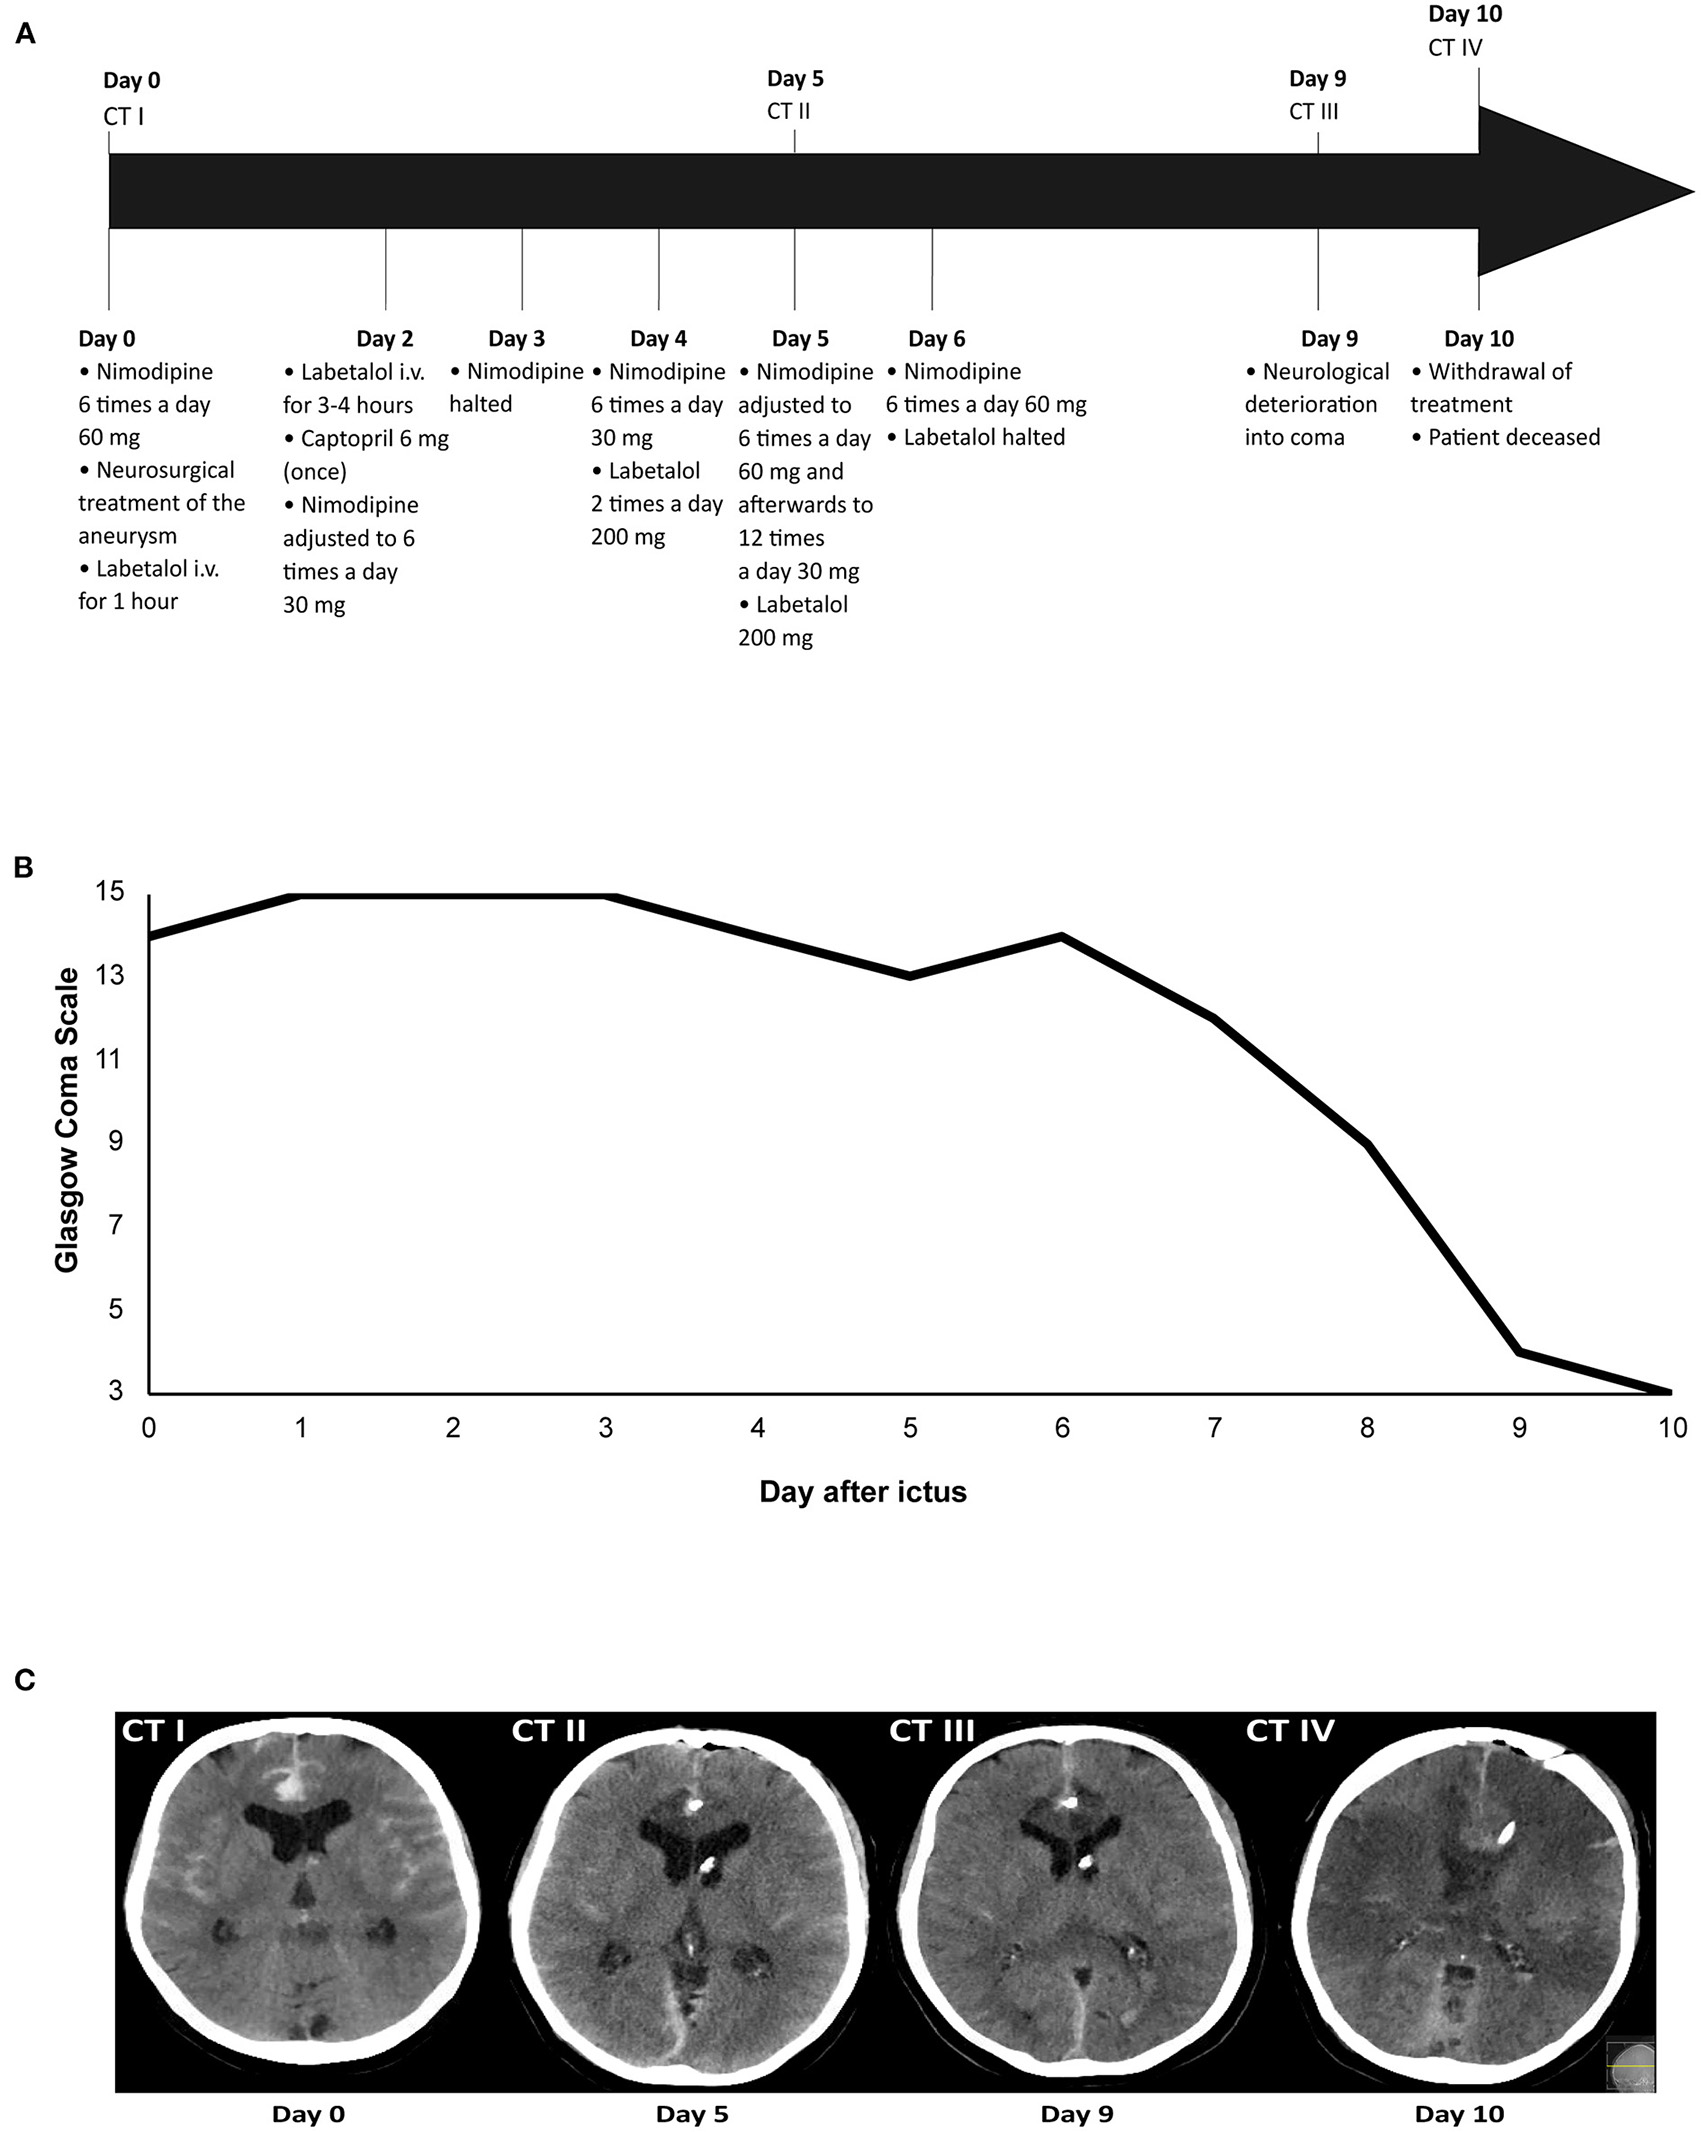

Figure 1

Illustrative case of a patient with devastating DCI. Time overview of: (A) Blood pressure medication adjustments and computed tomography (CT) scans; (B) Glasgow Coma Scale score; and (C) Ischemic lesions due to delayed cerebral ischemia on CT. The patient was admitted on day 0 and received nimodipine 6 times a day 60 mg. After neurosurgical treatment of the aneurysm on day 0, labetalol i.v. was administered for 1 h due to a high blood pressure, after which it was halted. Administration of nimodipine 6 times a day 60 mg continued. On day 2, labetalol i.v. was restarted because of a high blood pressure, but after 3–4 h labetalol was tapered and halted. Captopril 6 mg was administered once to avert a rise in blood pressure after labetalol was halted. Administration of nimodipine 60 mg resulted in a diastolic blood pressure drop of ≥10 mmHg, after which nimodipine dosing was lowered to 6 times a day 30 mg. On day 3, nimodipine administration was halted because of a drop in diastolic blood pressure ≥10 mmHg. After nimodipine administration was halted for 12 h, it was restarted again on day 4 at a dosage of 6 times a day 30 mg. Because of persistent systolic blood pressures >200 mmHg on day 4, the patient received labetalol 2 times a day 200 mg. On day 5, nimodipine dosing was increased to 6 times a day 60 mg, after which it was adjusted to 12 times a day 30 mg due to a drop in diastolic blood pressure ≥10 mmHg. The patient also received labetalol 200 mg. On day 6, nimodipine dosing was increased again to 6 times a day 60 mg and labetalol was halted as it was decided to accept systolic blood pressures >200 mm Hg. On day 9, the patient deteriorated into coma due to delayed cerebral ischemia. The patient was intubated and transferred to the ICU. On day 10, the decision was made to withdraw treatment, after which the patient was extubated. The patient died on day 10 after ictus.